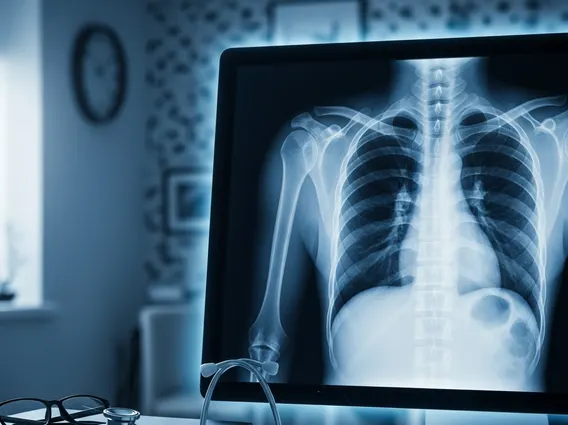

How Does a Chest X-Ray Work?

Understanding how does a chest x-ray work involves grasping the principles of radiation. During the procedure, a machine sends a controlled beam of X-rays through the patient’s chest. Different tissues absorb X-rays at varying rates. For instance, dense structures like bones absorb more X-rays and appear white on the image. Soft tissues such as the lungs, which are filled with air, absorb fewer X-rays and appear darker. The X-rays that pass through the body are captured by a special detector, either a photographic film or a digital sensor, which then creates the visual image. This rapid process typically takes only a few seconds.